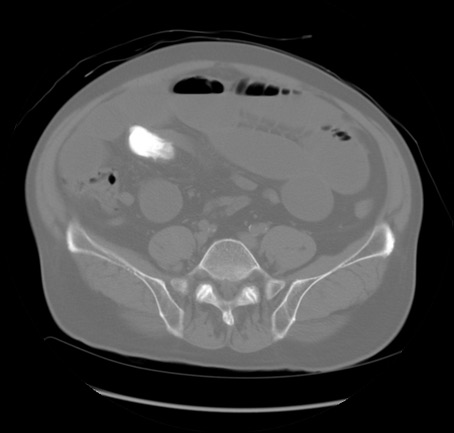

冠状断像

矢状断像